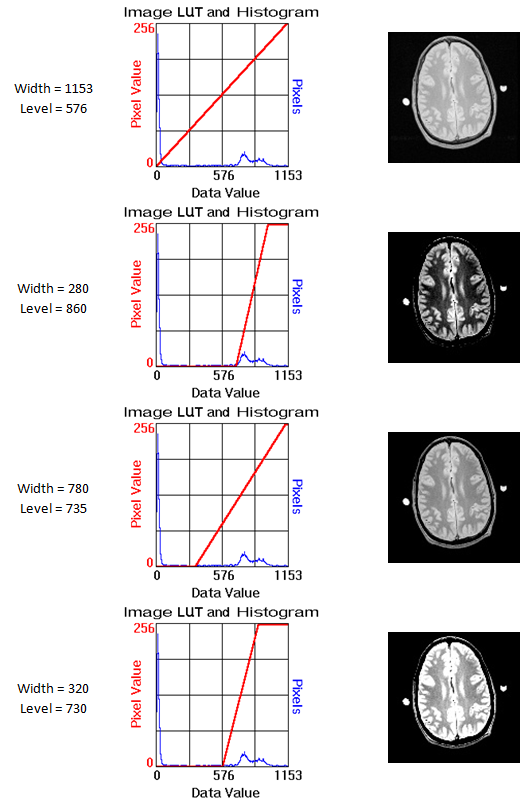

8.2. Look-Up Table (LUT)

Как уже упоминалось ранее, значения пикселей слайсов исследования лежат в достаточно широком диапазоне. Обычно используется Unsigned Integer, т.е. максимальный диапазон составляет [0, 32767]. Реальный диапазон для каждого исследования (и даже для каждой серии исследования) свой. При этом значения распределяются неравномерно – чаще по мультимодальному распределению с сильным скосом влево и длинным хвостом.

Для того чтобы такие данные можно было отображать, например, на 8-битном экране, разработана схема Look-Up Table (LUT), которая определяет, каким образом значения переводятся в диапазон [0, 255] с сохранением максимального контраста в нужной области. Схема задается двумя параметрами:

Ширина (Width) – диапазон значений, которые остаются ненулевыми,

Уровень яркости (Level) – положение середины диапазона на шкале значений.

Все значения, которые попадают в выбранный диапазон, преобразуются в [0, 255] по линейному закону.

Выбор параметров позволяет с максимальным контрастом отобразить требуемую область изображения.

Эта схема, разработанная для операторов томографов и врачей, полезна и для DS-задач в качестве осмысленного преобразования исходных значений в диапазон [0, 255]. Параметры LUT могут быть подобраны экспериментально или по результатам анализа распределений пикселей в зоне интереса для каждой решаемой задачи.